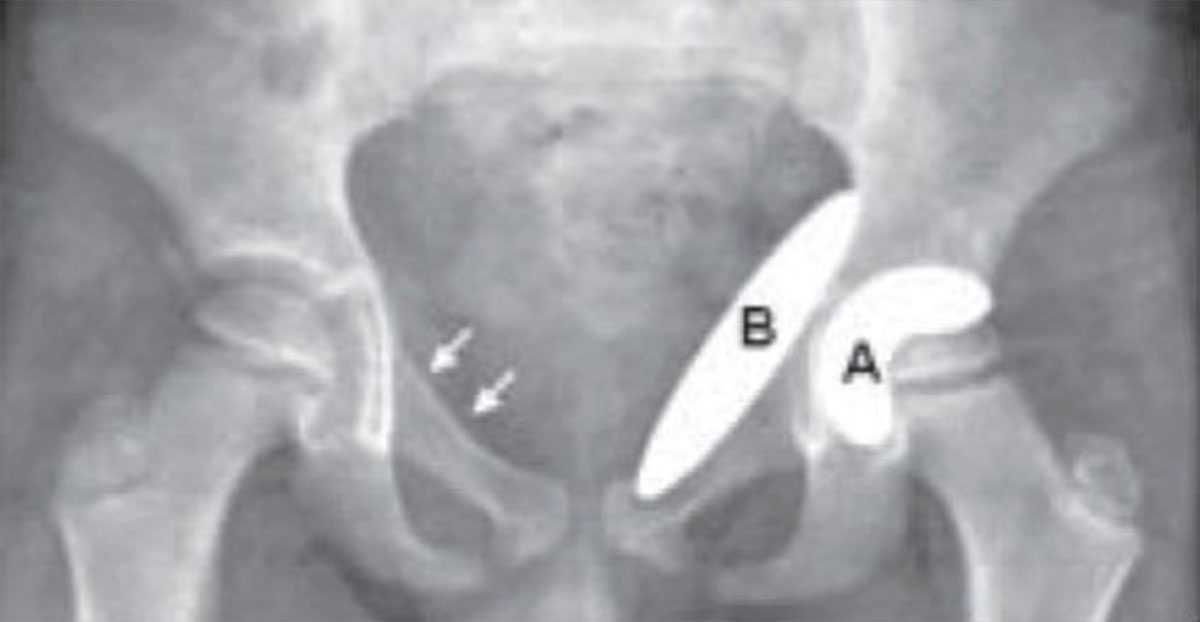

Con el paso del tiempo los huesos se debilitan, y una de las mayores causas de fracturas de cadera son las caídas, que terminan con golpes simples, lesionando gravemente a las personas mayores, porque sus huesos son mucho más delgados.

Esto sucede porque al debilitarse el sistema óseo los huesos pierden calcio, y en su mayor parte, ésta pérdida responde a la conocida enfermedad llamada osteoporosis, de la que hemos hablado en otras oportunidades. Al padecer una enfermedad como la osteoporosis si una persona se golpea o mucho peor se cae, las posibilidades de que sufra una fractura son casi inevitables.

La mayoría de las fracturas de cadera son provocadas por estas dos causas, osteoporosis, un golpe o caída. Las mujeres lamentablemente estamos mucho mas propensas a este tipo de inconvenientes, dado que durante la menopausia se aceleran drásticamente los procesos de descalcificación, por la falta de producción de estrógenos.

Esto incrementa las posibilidades de fractura de cadera, sobre todo en personas que consumen excesivamente alcohol, y grandes cantidades de cafeína, no practican ningún tipo de deportes o actividad física, padecen de bajo peso corporal, son de alta estatura, tienen problemas de visión, fuman, o consumen medicamentos, pueden provocar pérdida de masa ósea.